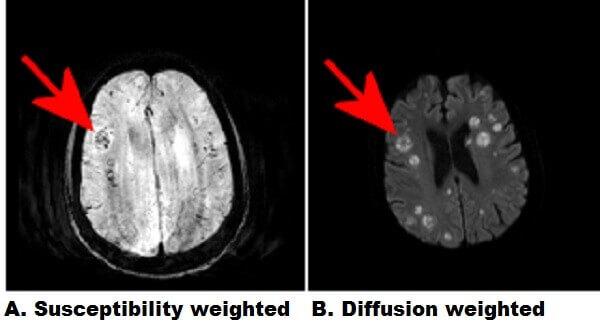

Figure 1: Red arrows. A : Axial susceptibility weighted images demonstrate multifocal regions of decreased signal (increased susceptibility) suggestive of petechial hemorrhage. B : The lesions demonstrate restricted diffusion (ADC signal is also decreased) and are situated at the grey-white junction. C : The lesions demonstrate increased T2/FLAIR signal with relatively little vasogenic edema.

There is an extensive differential for multifocal T2/FlAIR hyperintense lesions in the brain parenchyma including neoplasm (metastasis, lymphoma), infection (abscess, septic emboli), infarct (vasculitis), trauma (diffuse axonal injury) and demyelinating disease (multiple sclerosis). The peripheral distribution at the grey white junction follows regions of greatest blood flow within the brain suggesting a systemic origin like septic emboli and metastasis.

Neoplasms generally incite significant vasogenic edema and lack central restricted diffusion, which suggests an infectious process in this case. Septic emboli are infected embolic debris that originate most commonly from central venous cathethers, thrombophelbitis and endocarditis. Introvenous drug users and immunocompromised patients are predisposed. Multiple cavitary pulmonary lesions can also result from septic emboli.